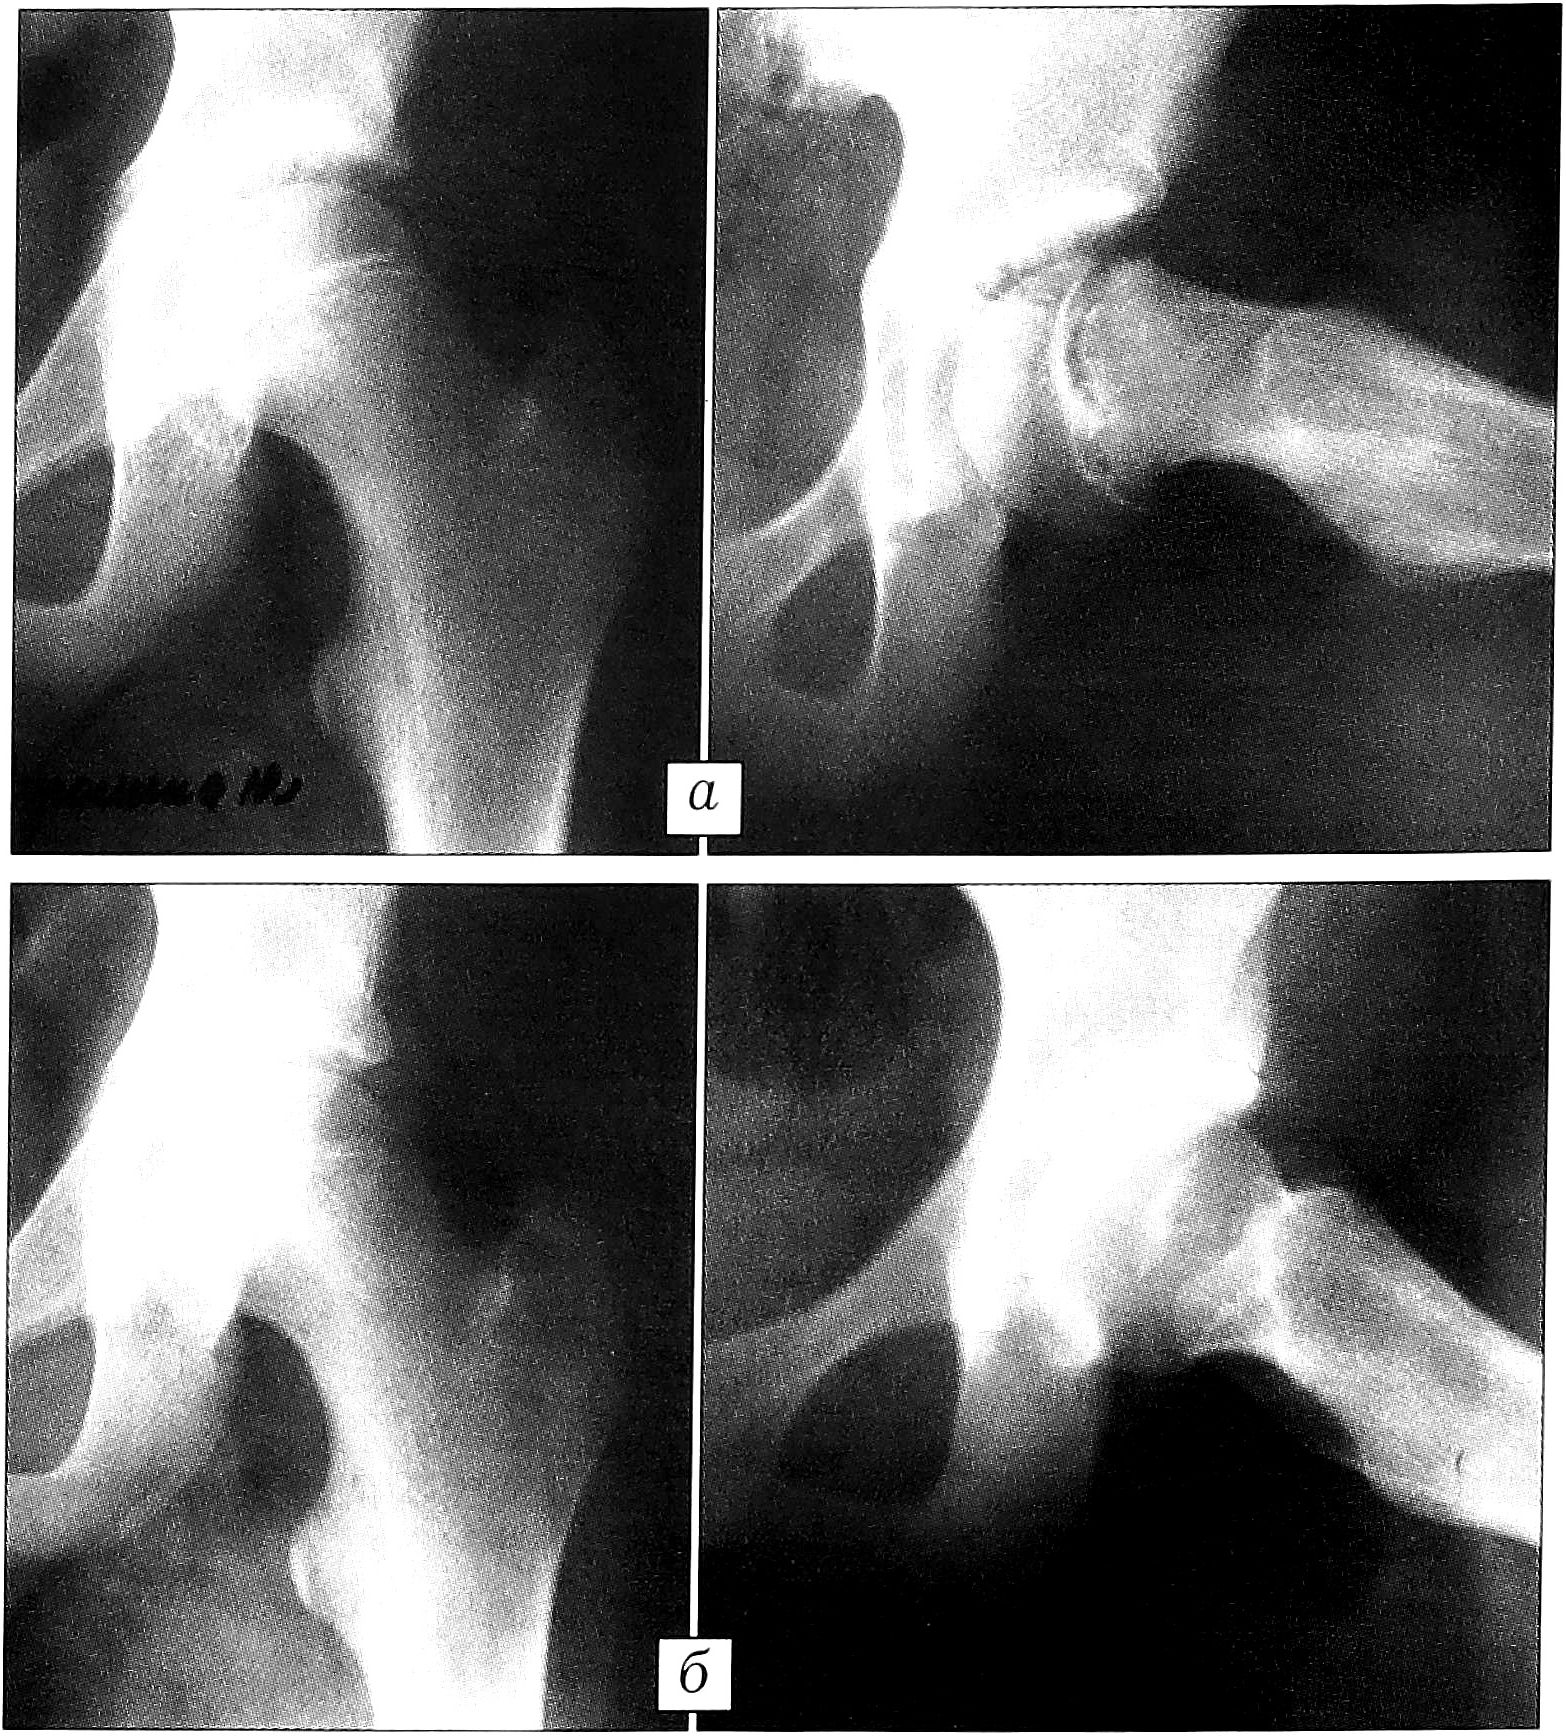

Больная Б.,10 лет, поступила с жалобами на боль в области левого тазобедренного сустава, усиливающуюся при физической нагрузке и иррадиирующую в коленный сустав, хромоту. Заболевание началось около 2 мес назад, когда появились боли в области левого коленного сустава. Наблюдалась в поликлинике по месту жительства. При поступлении: болезненность при пальпации в областей левого тазобедренного сустава, резкое ограничение внутренней ротации, гипотрофия мышц бедра на 1,5 см по окружности. На рентгенограммах левого тазобедренного сустава определяется линия резорбции в субхондральной зоне и увеличение шеечно-эпифизарного угла до 22° (рис. 1, а). Компьютерная томография уточнила протяженность зоны резорбции кости и взаимоотношение костных фрагментов. Диагноз: юношеский эпифизеолиз головки левой бедренной кости I степени. После 2 нед скелетного вытяжения анатомические взаимоотношения костных фрагментов восстановлены. В последующем проводилась электростимуляция остеогенеза в течение 38 дней в катодном режиме в сочетании с применением остеогенона по 1 таблетке 2 раза в день. В результате лечения зона резорбции исчезла, появились признаки структурализации элементов костной ткани (рис. 1, б). Больной назначены ЛФК, массаж, физиотерапия. Выписана на амбулаторное лечение в удовлетворительном состоянии с полным объемом движений в тазобедренных суставах. Через 4 мес выполнена компьютерная томография (рис. 2), показавшая восстановление структуры кости в субхондральной зоне. Разрешена нагрузка на больную ногу.

Рис. 1. Рентгенограммы левого тазобедренного сустава (в прямой проекции и в проекции по Lauenstein) больной Б. 10 лет. Диагноз: юношеский эпифизеолиз головки бедренной кости. а — до начала, б — после окончания электростимуляции остеогенеза.